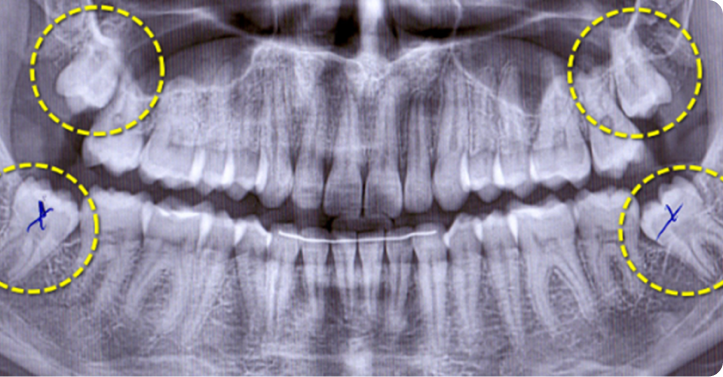

Дистоповані чи ретиновані зуби мудрості

Цей етап передбачає огляд ротової порожнини пацієнта, проведення рентгеноскопії задля прийняття рішення щодо доцільності видалення зуба.